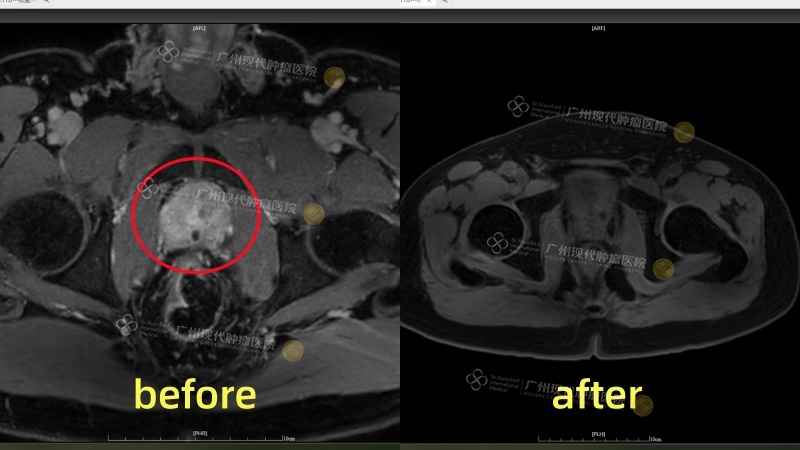

回国后他定期复查,每一次PSA指标的下降都让他信心倍增。最新MRI显示:肿瘤明显缩小,几乎消失。“我最感激的是,我没有出现尿失禁,也没有身体功能受损。我还是原来的我,只是身体里不再藏着一颗‘定时炸弹’。”他说这些话时,声音沉稳却带着一丝颤动。治疗不仅抑制了癌细胞,更守住了他作为父亲、丈夫的责任和尊严。

微创治疗后,约3cm前列腺肿瘤已接近“完全消失”